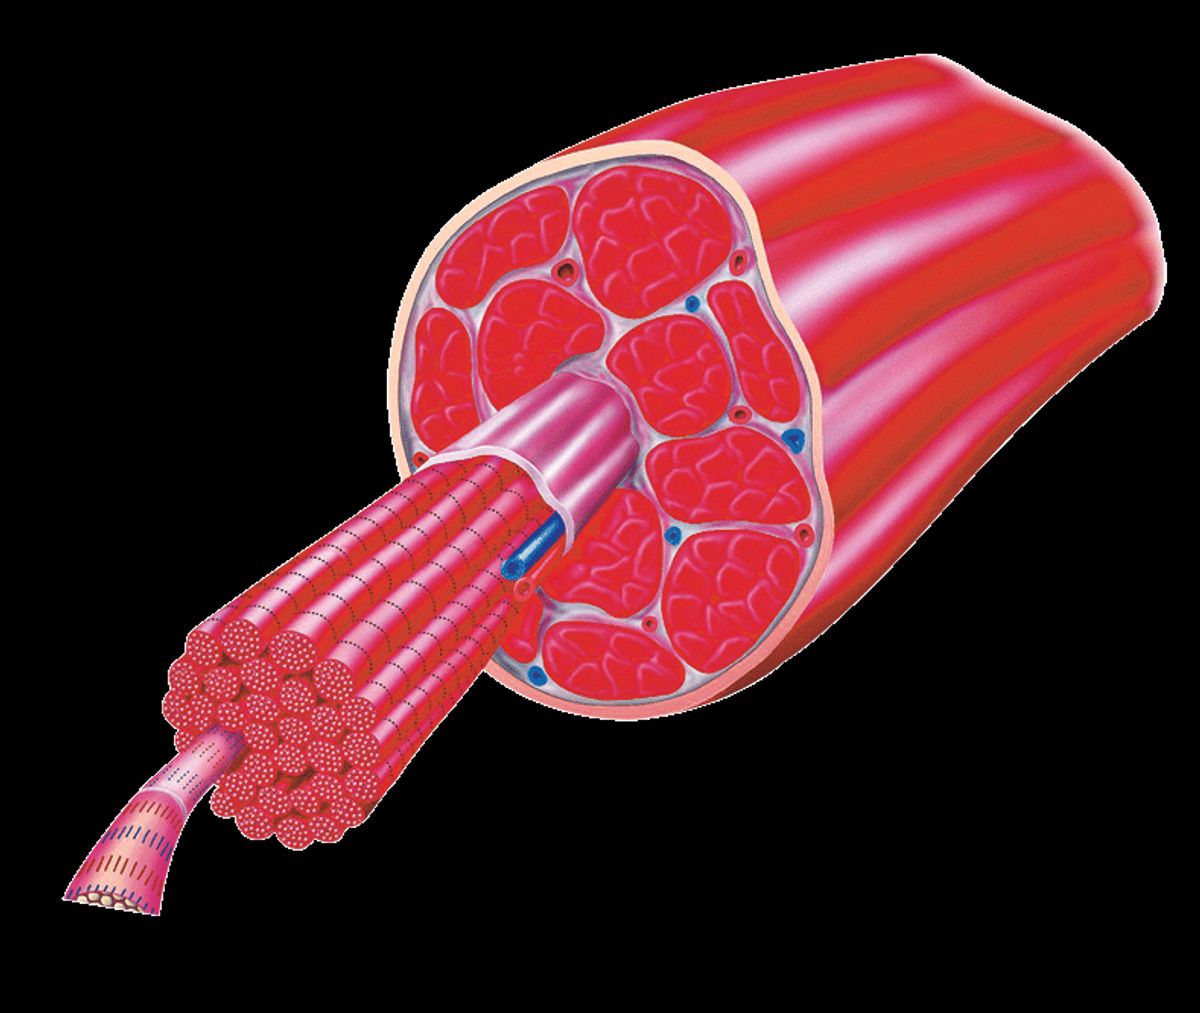

„Eine ausreichende Zeit des Auskurierens ist extrem wichtig bei Muskelverletzungen“, stellt Dr. Thorsten Rarreck, Mannschaftsarzt des FC Schalke 04, klar. Muskel stark überdehnt: Zunächst mal ist aber die Diagnose entscheidend, denn grundsätzlich liegt allen Muskelverletzungen dieselbe Ursache zugrunde: eine Dehnung des Muskels, die über das „normal verträgliche“ Maß hinausgeht. Doch was genau unterscheidet einen Bündelriss von Zerrung oder Faserriss? Was genau passiert dabei in der Muskulatur? Und was sind die möglichen Folgen? Hier gibts die Antworten!!!

"Die Art des Schmerzes hängt zunächst mal vom Patienten ab. Allerdings gibt es je nach Schwere der Muskelverletzung typische Muster", erklärt Dr. Thorsten Rarreck, der Teamarzt von Schalke 04. Während sich etwa bei einer Zerrung der Muskel kurz krampfartig zusammenzieht (ohne starken Schmerz), fühlt man beim Muskelfaser- oder Muskelbündelriss auf Anhieb einen deutlichen, schmerzhaften Stich, der die Zerstöung im Muskel erahnen lässt.